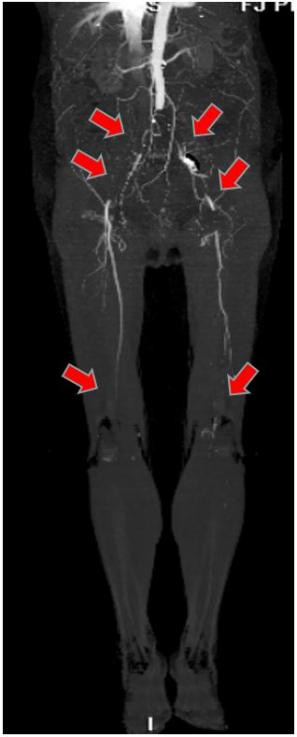

经过CTA证实,伊女士出现的是腹主动脉骑跨栓,从腹主动脉下段分叉开始都出现了不同程度的栓塞,双下肢出现了严重的缺血。

图中箭头所示:术前CTA提示腹主动脉双髂动脉骑跨栓,腹主动脉下段及双髂动脉血流中断